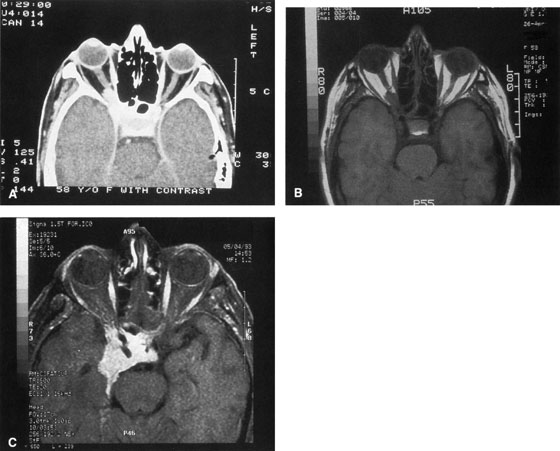

Valuable information about the nature and extent of an orbital pathologic process is provided by imaging studies such as computed tomography (CT) scan, magnetic resonance imaging (MRI), and orbital echography. Better spatial resolution, ready accessibility, and lower cost make CT the preferred choice for orbital imaging in most cases. Orbital fat provides a natural contrast between most adjacent orbital structures on CT scanning, and orbital bones are visualized well. Computed tomography is essential for evaluation of the orbital bones because they cannot be imaged with MRI. Direct coronal or sagittal images are important to identify the relationship of a lesion to the optic nerve so that the surgical approach can be planned to avoid traversing the optic nerve (Fig. 1).

Fig. 1. A. Axial CT scan demonstrating a large, well-encapsulated lesion in the orbital apex. Coronal (B) and sagittal (C) scans demonstrate that the mass lies inferior and medial to the optic nerve within the intraconal space. This information is useful in planning the surgical approach to the mass, which should avoid traversing the optic nerve.